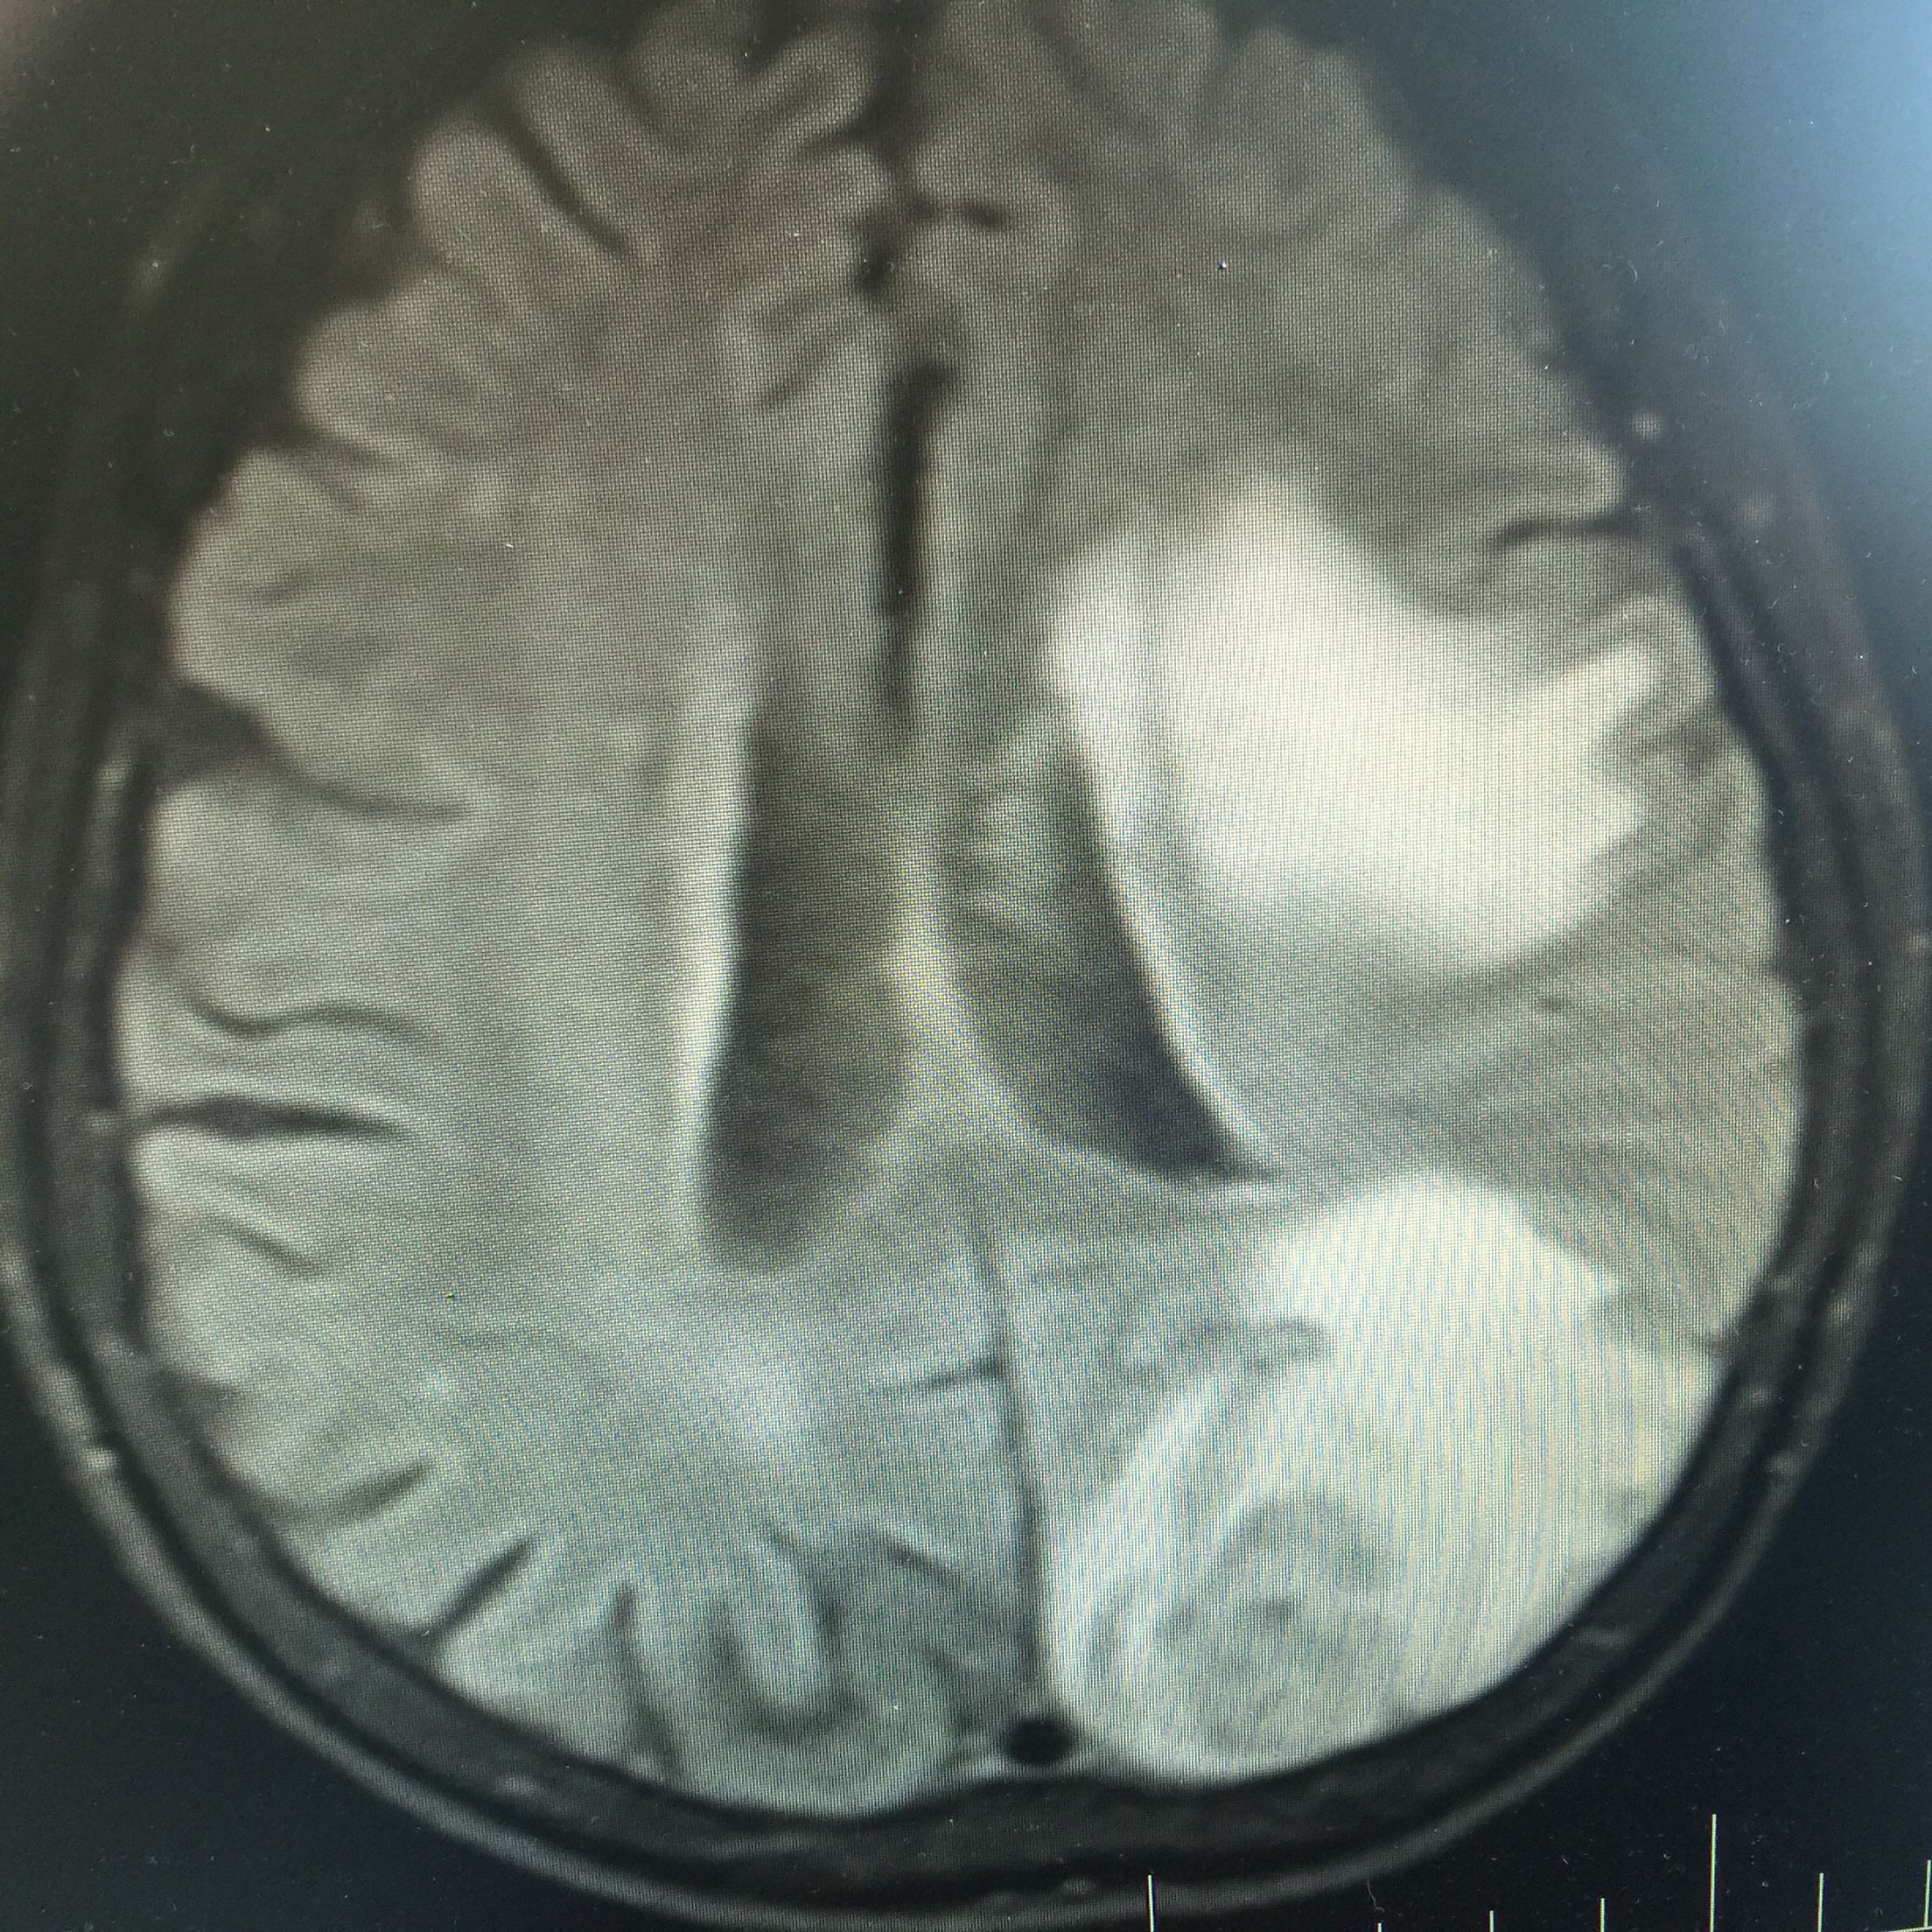

1.女,81岁,以“右侧肢体无力3天”入院。 2.现病史:3天前无诱因出现右侧肢体无力,右上肢抬举费力,右下肢步行拖拉,无抽搐,无意识障碍! 3.既往史:2016年肺穿刺活检,免疫组化为腺癌!已合并第五、六椎体转移、左肾上腺转移,行灌注介入治疗。

查体:血压:130/80mmHg,两肺呼吸音清,未闻及啰音,心率98次/分,律齐,未及杂音,双下肢无水肿。神经系统查体:意识清,双侧瞳孔等大正圆,直径约3.0mm,对光反射灵敏,无面舌瘫,右侧肢体肌力4级,腱反射减弱,Babinski征R+L-。

左肺腺癌 骨转移、双肺门及纵膈淋巴结转移、左肾上腺转移、脑转移! 治疗:对称、支持治疗!